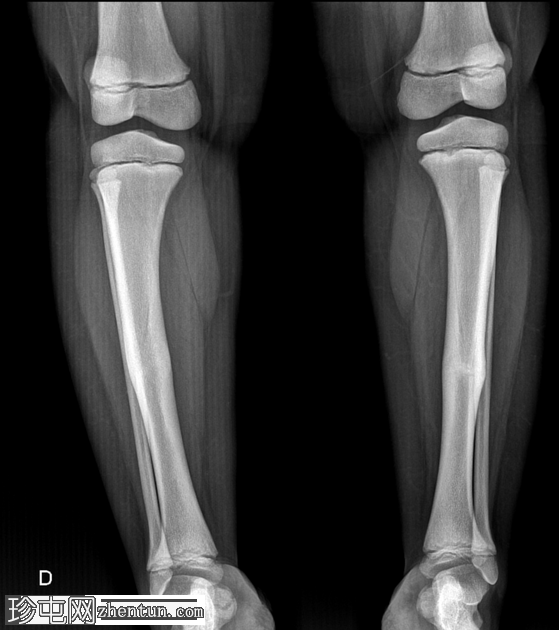

X光片

正面

侧面

弥漫性骨密度增高。

长骨髓质变窄。

右股骨不完全性骨折,骨折后功能不全。

双侧胫骨骨干先前骨折后出现骨重塑。